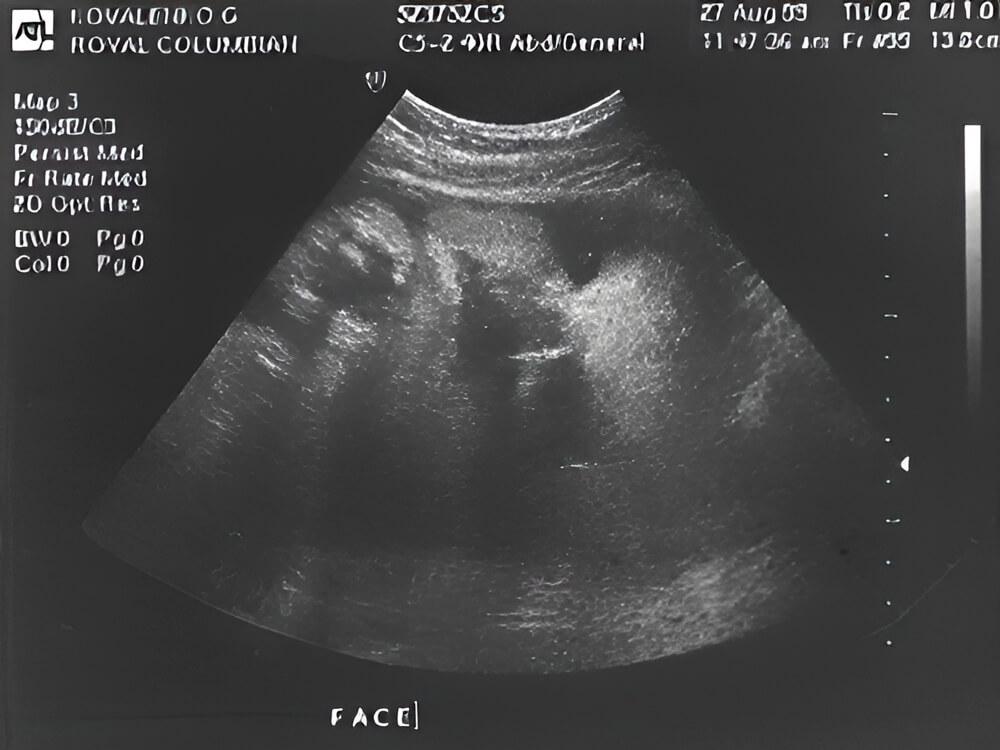

¿Qué se puede ver en la ecografía/ultrasonido?

En esta imagen, el bebé está acostado boca arriba con el lado derecho hacia la pantalla. Su cabeza, brazos, piernas y estómago son visibles.